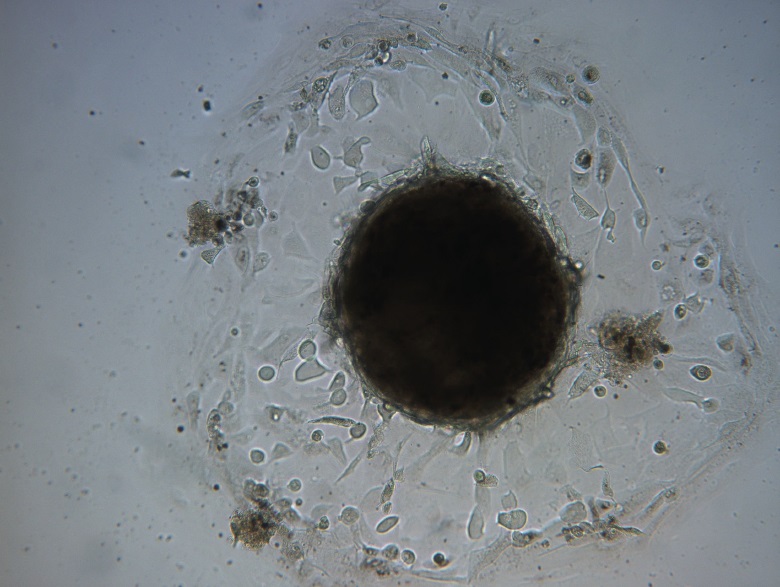

Para el cultivo de las células primordiales de la superficie ocular se tomaron muestras del anillo esclero-corneal de una córnea de banco de tejidos y, luego, la trepanación para la obtención del botón corneal a ser implantado en el ojo de un paciente que se hallaba en lista de espera del CUADIO.

Respecto al procesamiento y cultivo, las muestran se recibieron y se lavaron con Solución de buffer PBS estéril y luego se disgregaron en piezas pequeñas con bisturí estéril y se trataron con Tripsina durante 15 min a 37C. La suspensión de células resultantes y las piezas se sembraron en placas de cultivo conteniendo medio DMEM:F12 (GIBCO) suplementado con B27 (GIBCO) y factores de crecimiento FGF y EGF (SIGMA) siguiendo procesos de la bibliografía y propios del laboratorio (Montaner et al 2018, Magaquian et al 2021 y Delgado et al 2023). Todo el procedimiento se realizó en flujo laminar BSLa.

Los cultivos se incubaron es estufas gaseadas CO2(5%) y a 37C por 20 días. Cada tres días el medio se suplementó con factores de crecimiento.

Diariamente, se observaron en microscopio óptico invertido para visualizar las células, su morfología y la

ausencia de contaminaciones bacterianas.